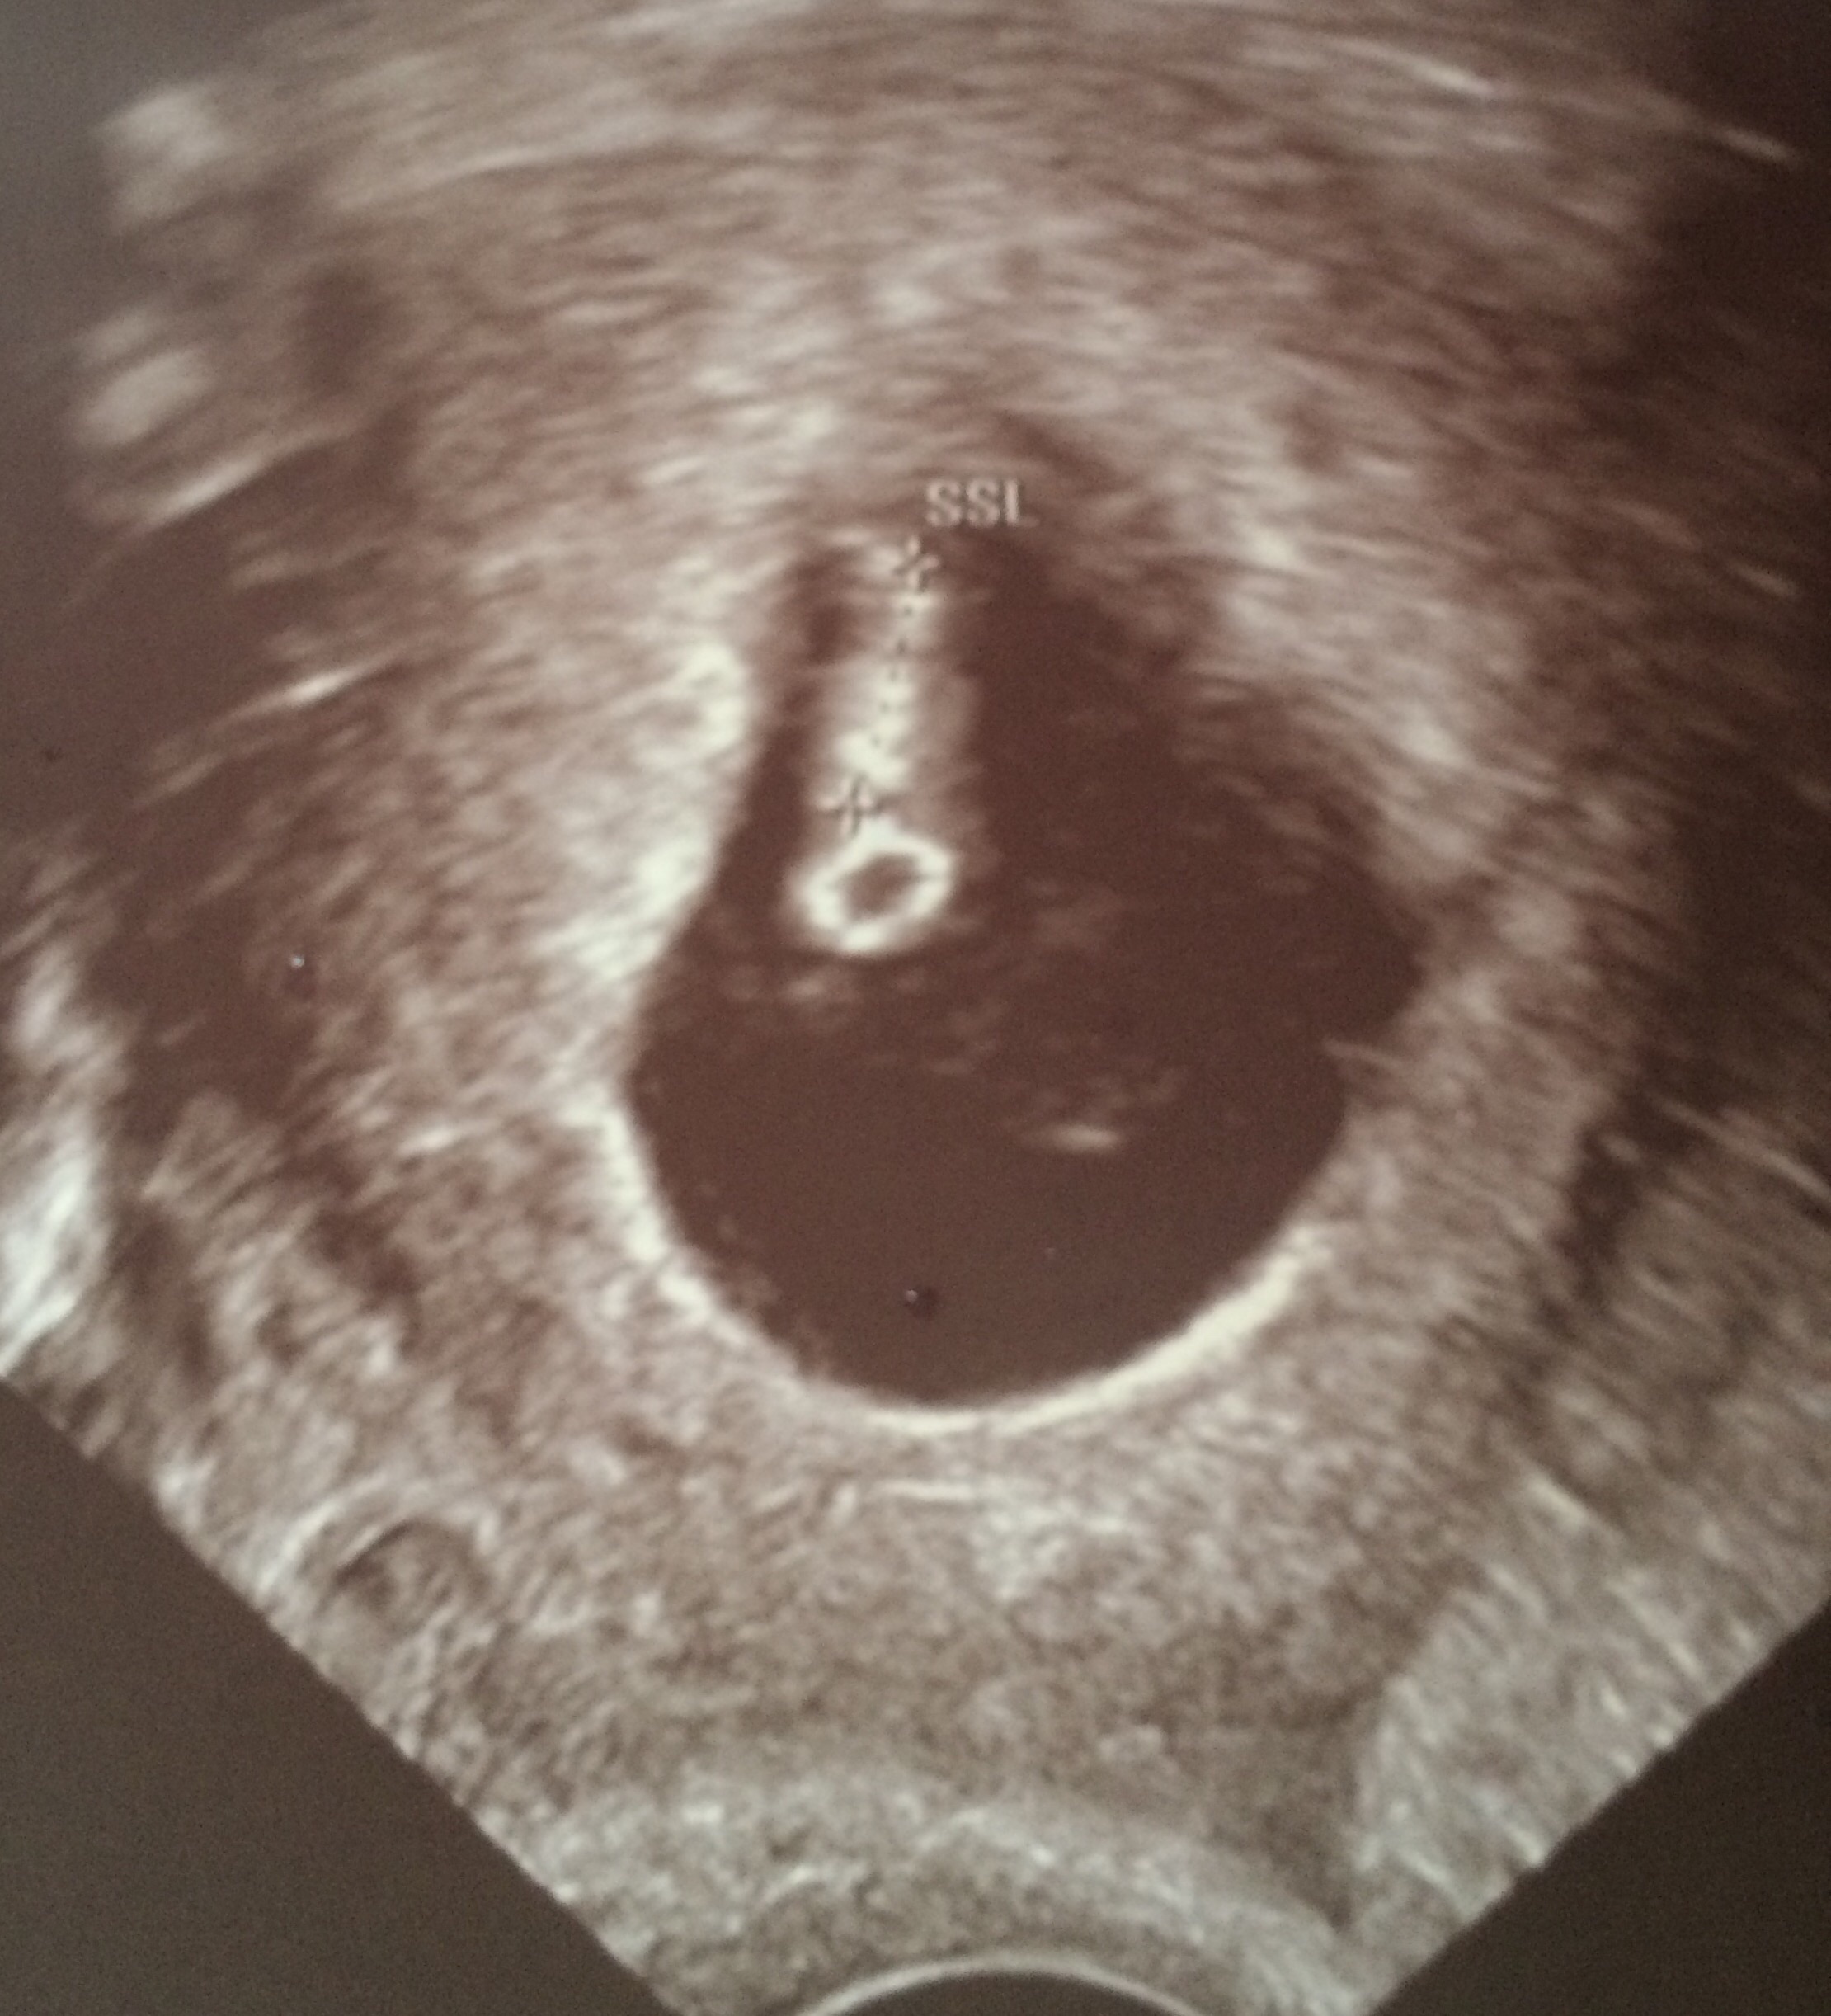

This was a transabdominal ultrasound.

Our little one today! 6w1d

108HB